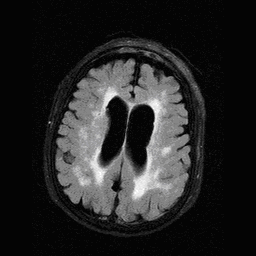

Multiple sclerosis typically appears with lesions presenting in the hemispheric white matter with a periventricular predilection. Other less usual locations for MS lesions include the cerebellum and the pons.

The method of choice for the imaging of multiple sclerosis is MRI. MS lesions secondary to their increased water content appear as increased signal intensity lesions on (T2 weighted), PD images and on FLAIR sequence.